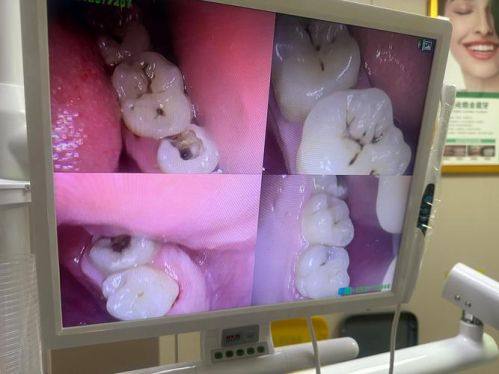

1. 特色儿童口腔科:配备专门的儿牙治疗医师与安抚医师,打造充满童趣的诊疗环境,儿童诊室牙椅采用卡通形象设计,能够有效缓解儿童看牙时的紧张恐惧情绪。可开展儿童龋病防治、牙髓治疗、早期错颌畸形干预等全品类儿童口腔诊疗项目,同时拥有传统活动矫治器、罗慕、ETA、正雅、时代天使、隐适美等多种早期干预矫治器,适配不同儿童牙齿畸形矫治需求。